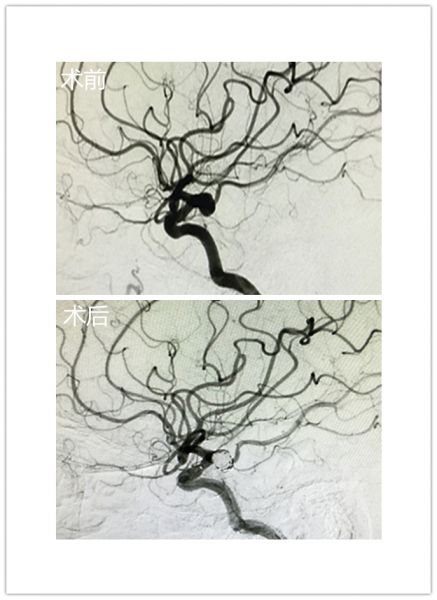

钟女士,66岁,因突发头痛5小时入院。入院后完善脑血管CTA提示:1、双侧颈内动脉后交通动脉瘤;2、蛛网膜下腔出血。神经外科二病区主任朱英杰立即组织讨论,认为患者颅内动脉瘤破裂出血入院,且为双侧颈内动脉后交通动脉瘤,病情凶险,死亡率极高,治疗难度大。经与患者家属多次积极沟通后,家属态度坚决并要求积极治疗,神经外科脑血管病团队通过精心准备,术前反复讨论并演练手术过程,在介入科、麻醉科多学科协作下,于全麻下行双侧颈内动脉后交通动脉瘤栓塞治疗,手术顺利。术后通过医护人员精心治疗和护理,钟女士恢复良好,未见明显并发症出现。